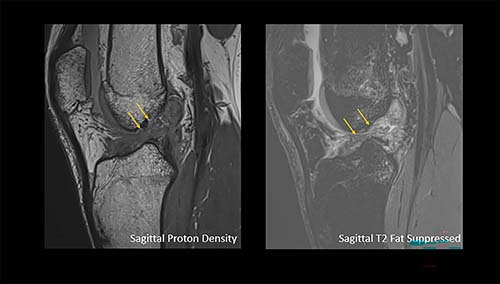

Figure 3. Arrows show a complete anterior cruciate ligament rupture in an 18-year-old male who had a knee injury while playing football.